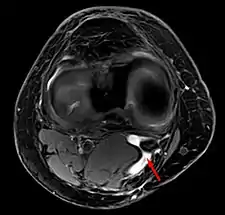

quiste de Baker en MRI axial con comunicación entre el músculo semimenbranoso y el the músculo gastrocnemius.